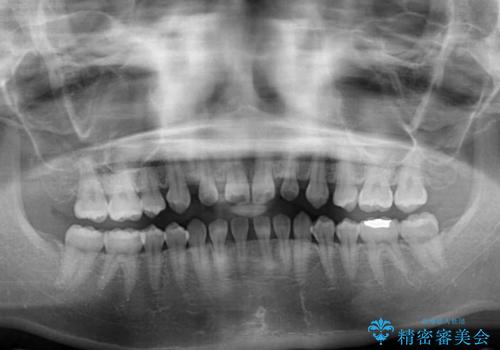

- 歯の欠損による隙間だらけの歯並びを気にして来院された患者様です。

上顎左右1本ずつ欠損していたため、歯列矯正により欠損部位にスペースを集め、その後欠損部位をインプラントにて補綴することとしました。